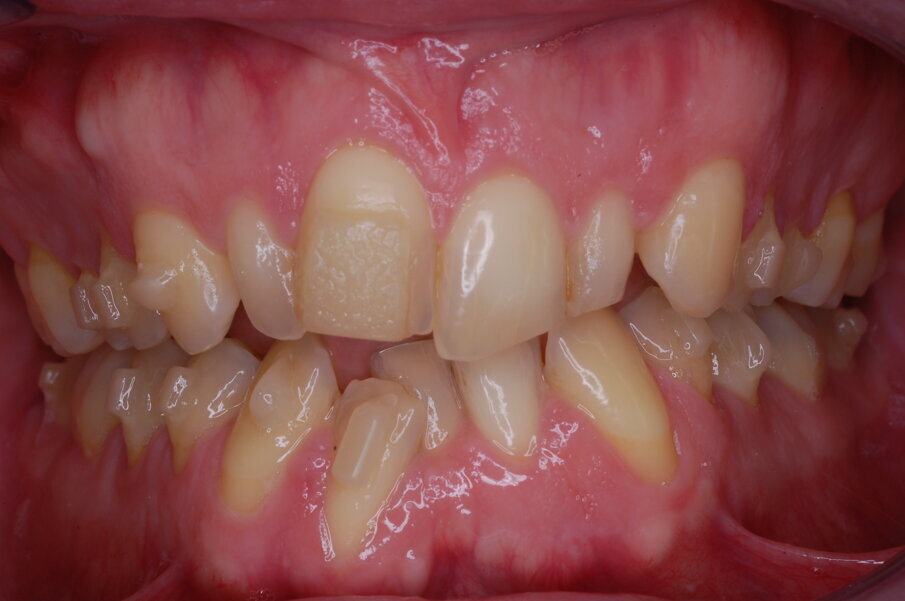

Diagnosi ed eziologia Un uomo sano di 39 anni si è presentato nel nostro studio ortodontico lamentando un aspetto dentale poco attraente e la paura della chirurgia ortognatica proposta da un altro ortodontista. Clinicamente, il profilo del paziente era rettilineo e la vista frontale non mostrava alcuna asimmetria facciale. L’esame funzionale non ha rivelato alcuna deviazione mandibolare o riduzione dei movimenti. Il paziente non aveva dolori articolari e non sono stati rilevati rumori articolari. Era presente una lieve occlusione molare bilaterale di Classe II, un morso aperto e un grave affollamento in entrambe le arcate. L’affollamento era particolarmente grave nell’arcata mandibolare, sebbene mancasse l’incisivo centrale mandibolare destro. Gli incisivi mascellari erano di piccole dimensioni, suggerendo una discrepanza dell’indice di Bolton se fossero stati presenti tutti e quattro gli incisivi mandibolari. Erano inoltre presenti un morso incrociato nella regione dell’incisivo laterale superiore sinistro e una grave rotazione distale del secondo premolare mandibolare sinistro (Figg. 1-8).

Figg. 1-8_Fotografie facciali e intraorali pre-trattamento.